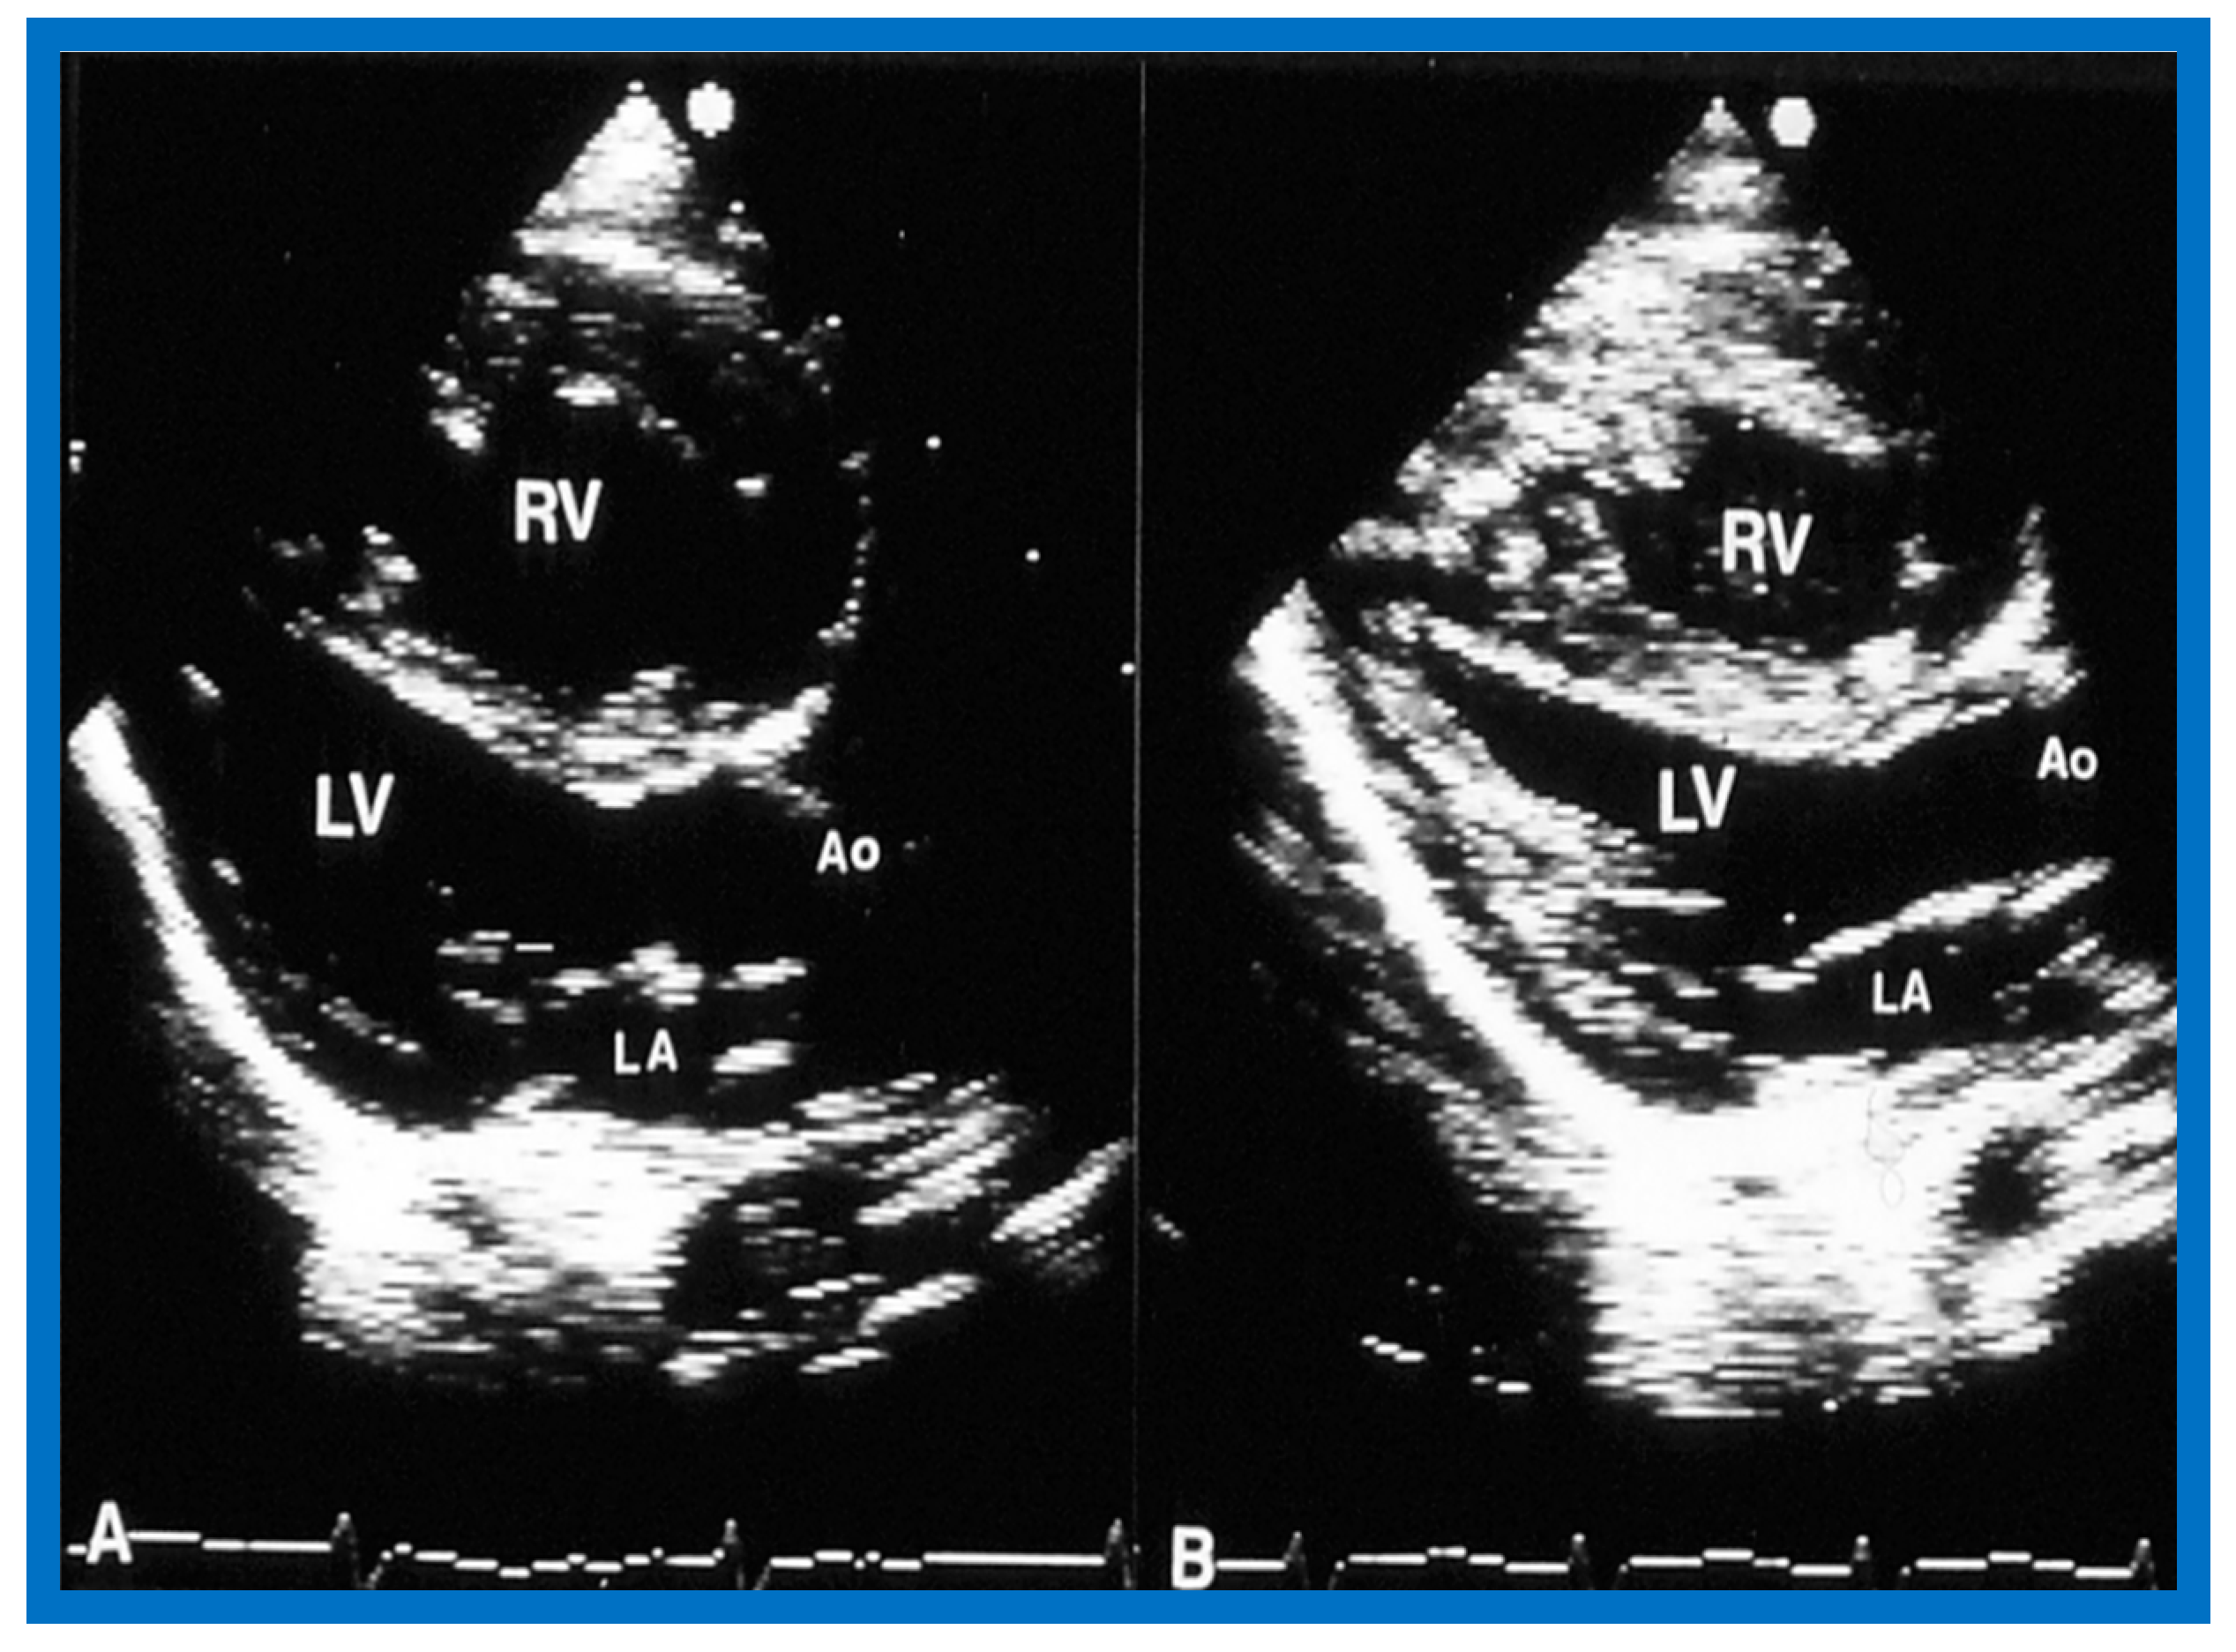

6.2.2. Ventricular Dimensions and Function

6.2.3. Re-Interventions and Actuarial Event-Free Rates